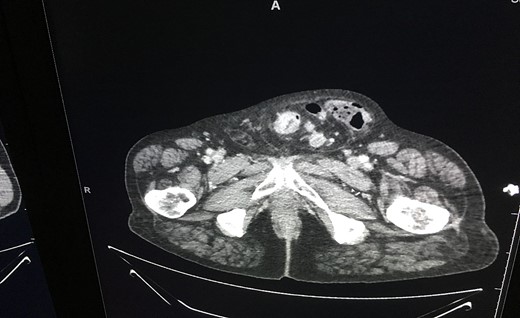

An ultrasound of the scrotum revealed ‘large left inguinal scrotal hernia containing omentum and bowel loops, on the right a high indirect inguinal hernia containing only fat tissue’ was described. A CT was subsequently performed, which revealed a likely primary sigmoid colon malignancy lying within the left-sided scrotal hernia and extensive liver metastasis (as seen in Fig. 2). The tumour contained within the hernia sac is illustrated in Fig. 3.